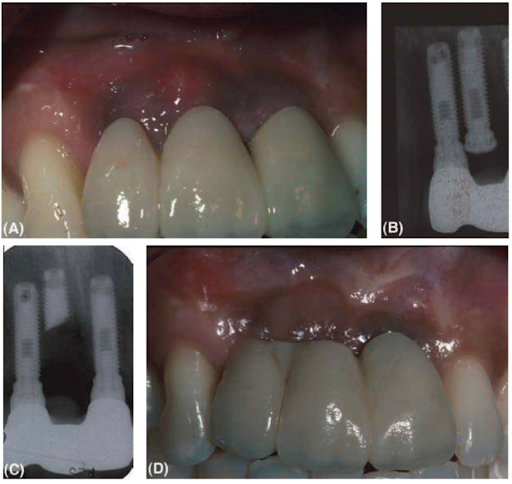

(A) Hình ảnh lâm sàng của cầu răng ba đơn vị trên implant thay thế cho rằng cửa bên phải và hai răng cửa giữa. Áp xe trên mô mềm tại vùng răng cửa giữa phải. Khởi đầu ba implant đã được cắm để thay thế cho mỗi đơn vị răng vị mất.

(B) Phim x quang cho thấy có một implant không sử dụng và chôn vùi dưới niêm mạc vùng răng cửa giữa phải, khá gần với implant răng cửa bên. Điều này đã dẫn tới nhiễm trùng niêm mạc trên đầu implant đã chôn vùi.

(C) Implant này không thể thực hiện được phục hình như một đơn vị độc lập và cũng không lấy ra được bằng mũi khoan Trephine để giải quyết nhiễm trùng. Do đó phần đầu implant đã được cắt và lấy ra ngoài, để lại phần chóp.

(D) Kết quả lành thương, ổ nhiễm trùng đã tiêu biến. Một mềm mất đi phải được bù trừ bằng cầu răng mới. Nếu chỉ đặt hai implant trong khoảng xương giới hạn thay vì ba implant thì ta đã có thể tránh được vấn đề này.

Trong những trường hợp nghiêm trọng khác cách giải quyết duy nhất là loại bỏ implant hoặc chôn vùi dưới niêm mạc. Phục hình được thiết kế và tạo ra kém có thể cần được thay mới nhưng trong một số trường hợp phải sửa lại vị trí implant cho đúng. Do đó phải tìm một phương án thỏa hiệp.